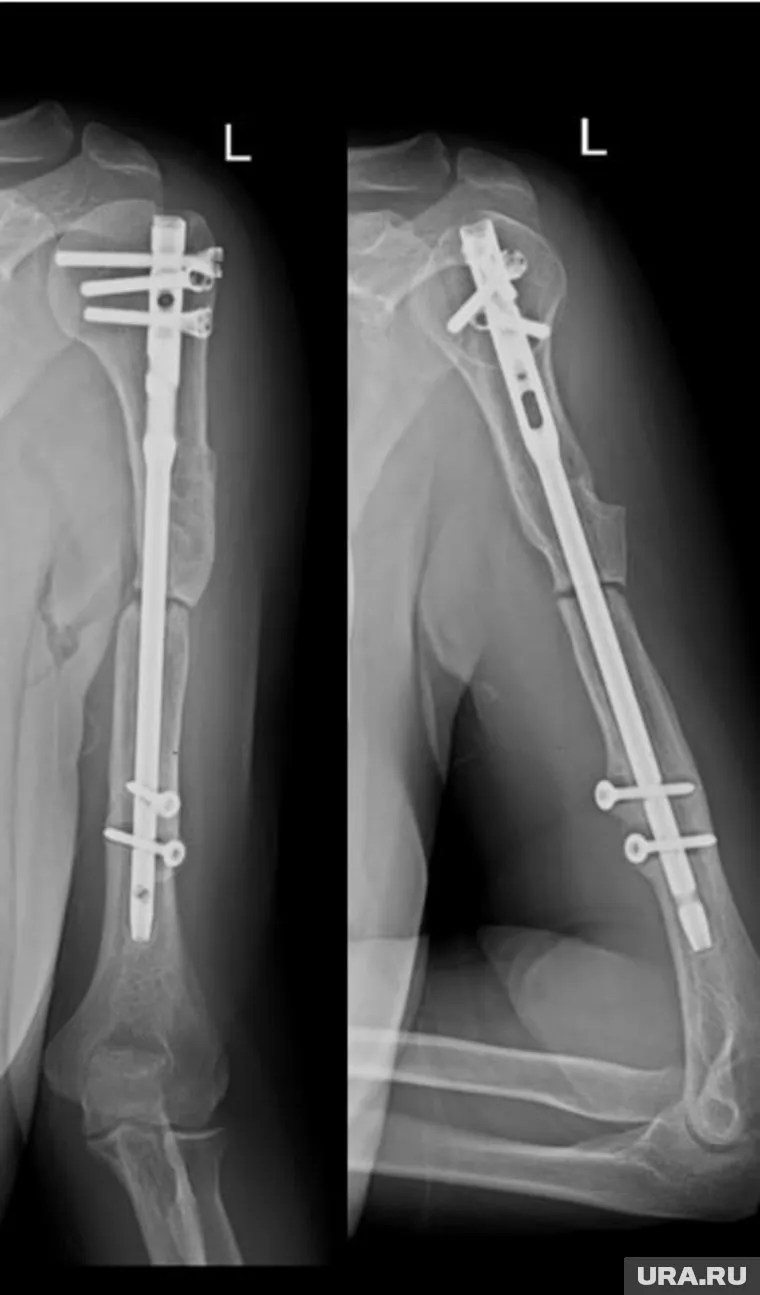

«37-летняя жительница Ставропольского края два года назад упала с высоты восьмого этажа, получила тяжелую сочетанную травму плечевой кости. По месту жительства молодой женщине была сделана операция с использованием интрамедуллярного остеосинтеза», — пишет ведомство. Однако добиться сращения костей не удалось — развился стойкий ложный сустав, а деформация плеча усиливалась. Врачи Центра Илизарова провели комплексное хирургическое лечение: удалили старую металлоконструкцию, устранили деформацию, выполнили остеотомию и локальный остеосинтез с применением аппарата Илизарова.

После операции состояние пациентки стабилизировалось, болевой синдром был устранен, а поврежденная конечность получила надежную фиксацию. На период дальнейшей фиксации в аппарате Илизарова женщина была выписана домой для амбулаторного лечения. За процессом восстановления будут наблюдать дистанционно: врачи центра регулярно анализируют рентгенограммы, присылаемые пациенткой, и контролируют динамику сращения кости.

Фото: tg-канал НМИЦ ТО имени академика Г.А. Илизарова Минздрава России